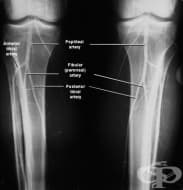

Артрограма

Aртрограма е изследване, което използва рентген за направата на серия снимки на дадена става, след к...